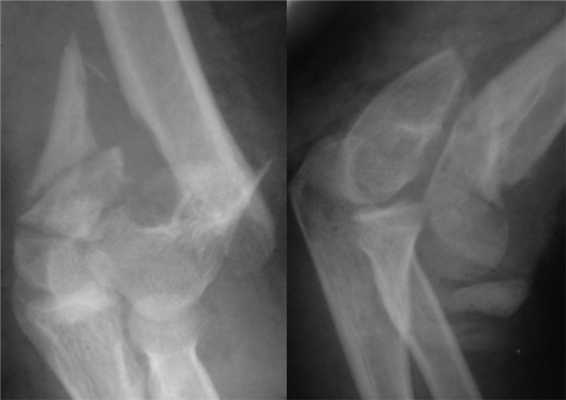

Больная П., 25 лет, поступила в стационар с жалобами на боли в левом локтевом суставе через 2 ч после травмы в результате падения на улице. При осмотре отмечены отек левого локтевого сустава, болезненность при пальпации, невозможность движений в суставе из-за боли. После клинико-рентгенологического обследования установлен диагноз: закрытый внутрисуставной оскольчатый чрезмежмыщелковый перелом левой плечевой кости со смещением отломков тип 13-С2 (рис. 2). Рисунок 2. Рентгенограммы больной П. с внутрисуставным оскольчатым чрезмежмыщелковым переломом левой плечевой кости со смещением отломков тип 13-С2.

Сосудистых и неврологических расстройств в дистальных отделах левой верхней конечности выявлено не было. При поступлении произведена анестезия места перелома, внешняя иммобилизация гипсовой лонгетной повязкой.

На следующий день под новокаиновым блоком плечевого сплетения произведена операция: закрытая репозиция и чрескостный остеосинтез левой плечевой кости спице-стержневым аппаратом внешней фиксации конструкции А.И. Городниченко. Через разрезы кожи и мягких тканей по наружной поверхности левого плеча длиной до 5 мм введено 2 кортикальных стержня в диафиз плечевой кости, один кортикальный и один спонгиозный стержень и 2 спицы с упорной площадкой в мыщелки и надмыщелки плечевой кости. После фиксации проксимальных стержней в аппарате под контролем электронно-оптического преобразователя произведена закрытая репозиция с помощью съемных рукояток с последующей стабилизацией дистальных стержней и спиц (рис. 3). Рисунок 3. Рентгенограммы больной П. после остеосинтеза левой плечевой кости спице-стержневым аппаратом. Кожа вокруг стержней ушита одиночными швами. Кровопотеря в ходе операции 20 мл. Продолжительность операции 40 мин.